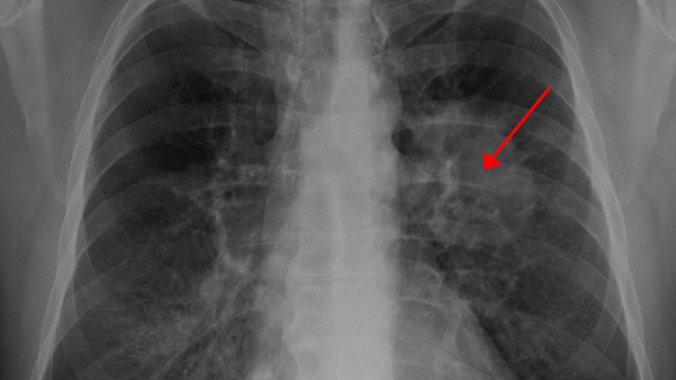

Za pacijente koji su u većem rizika, naša sagovornica preporučuje da jednom godišnje urade snimak pluća, a povremeno i niskodozni skener pluća kako bi bolest dijagnostikovali u ranoj fazi.

Smrtnost od karcinoma pluća u Srbiji je velika jer se bolest otkriva obično u odmakloj fazi. Tek u 15 do 20 odsto slučajeva bolest se otkrije u ranoj fazi kada postoji veće šansa za izlečenje.